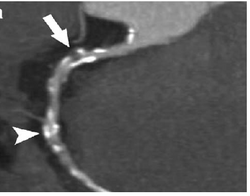

Image of contrast enhanced dual-source coronary CT-angiograph

Computed tomography angiography (CTA), an imaging methodology using a ring-shaped machine with an X-ray source spinning around the circular path so as to bathe the inner circle with a uniform and known X-ray density. Cardiology uses are growing with the incredible developments in CT technology. Currently, multidetector CT, specially the 64 detector-CT are allowing to make cardiac studies in just a few seconds (less than 10 seconds, depending on the equipment and protocol used). These images are reconstructed using algorithms and software.